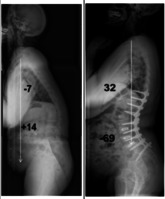

[오늘의 건강Tip] 추석에 만난 부모님, 허리가 앞으로 굽어져 있다면…?

"꼬부랑 할머니가~ 꼬부랑 고갯길을~ 꼬부랑 꼬부랑~ ♬"동요 ‘꼬부랑 할머니’의 가사 중 일부다. 왜 할머니는 꼬부랑 할머니가 되었을까? 원인은 바로 척추 후만증 때문이다. 척추 후만증은 등이 솟고 상체가 앞으로 기울어지는 척추의 변형이다. 무게 중심이 앞